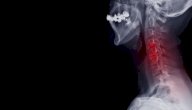

تتكوّن الأقراص الفقريّة عند الأطفال بنسبة خمسٍ وثمانين بالمئة من المياه بينما تقلّ هذه النّسبة بشكل طبيعي مع التقدّم في السنّ لتصل في عمر السّبعين إلى ما يقارب سبعين بالمئة. ومن الملاحظ أنّه مع خسارة المياه من الأقراص الفقريّة تُصبح أكثر عرضة للتشقّق والتمزّق، وتُعدّ هذه الأقراص غير قادرة على إصلاح نفسها، وذلك لعدم احتوائها على تغذية دمويّة بشكل مباشر.[٢] يُلاحَظ مع الوقت اهتراء الأقراص وبدء عمليّة التّدهور، حيث يقلّ الفراغ بين الفقرات وتُصبح جذور الأعصاب مضغوطة، وتُسمّى هذه العمليّة داء القُرص العُنُقي التنكّسي (بالإنجليزيّة: Cervical Degenerative Disk Disease)، ومع استمرار وتقدّم هذه العمليّة تُصبح الرّقبة أقلّ مرونةن ويبدو واضحاً الألم وازدياد الصّلابة في الرّقبة. ويظهر مرض دسك الرّقبة أو ما يُعرف علميّاً بالانزلاق الغضروفي العُنقي (بالإنجليزيّة: Cervical Disk Herniation) وعندما ينتفخ القرص للخارج أو ينفتح ومن ثمّ يُسبّب ضغطاً على جذور الأعصاب أو الحبل الشّوكي.[٣][٤]

يحتاج الطّبيب لمعرفة الأعراض التي ظهرت على المريض في الفترات السّابقة بالإضافة إلى الفحص السريري ليتسنّى له تشخيص المرض، بالإضافة إلى ذلك يمكن أن يحتاج الطّبيب عمل فحوصات تصويريّة متخصّصة لتشخيص أفضل لمرض الانزلاق الغضروفي العُنقي.[٤][٦]

ومن أبرز الفحوصات التّصويريّة:[٦]

- التّصوير بالرّنين المغناطيسي MRI (بالإنجليزيّة: Magnetic Resonance Imaging)؛ وهو أفضل وأول فحص لتشخيص الانزلاق الغضروفي حيث يستطيع تصوير أي جذر عصبي تعرض للضغط بسبب الانزلاق الغضروفي.

- الأشعّة المقطعيّة مع تصوير النّخاع (بالإنجليزيّة: CT scan with Myelogram)؛ بالرّغم من أن هذا الفحص حسّاس أكثر ولكن لا يتمّ استخدامه كأوّل فحص لأنه يُعتبر فحصاً جراحياً (بالإنجليزيّة: Invasive Test) فهو بحاجة لحقن صبغة تصوير النّخاع إلى القناة النّخاعيّة كجزء من إجراءات هذا الفحص.